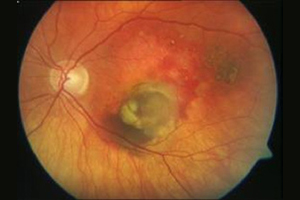

Augenhintergrund – Augenärztliche Gemeinschaftspraxis | Dr. Heuring, Dr. Jung & Kollegen

spätes Stadium einer AMD